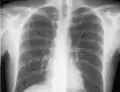

If a pneumothorax is suspected, an upright chest x-ray should be obtained. An upright chest x-ray is preferred because free air will migrate to the apex of the lung, where it is easily visualized. Of course, this is not always possible, particularly in critically ill patients in the intensive care unit. Radiographs obtained in the supine position fail to detect 25–50% of pneumothoraces.[6] Instead, bedside ultrasound is a superior method of detection in those too ill to obtain upright imaging.[3]

The line is then inserted using the Seldinger technique: a blunt guidewire is passed through the needle, then the needle is removed. A dilating device may be passed over the guidewire to expand the tract. Finally, the central line itself is then passed over the guidewire, which is then removed. All the lumens of the line are aspirated (to ensure that they are all positioned inside the vein) and flushed with either saline or heparin.[1] A chest X-ray may be performed afterwards to confirm that the line is positioned inside the superior vena cava and no pneumothorax was caused inadvertently. On anteroposterior X-rays, a catheter tip between 55 and 29 mm below the level of the carina is regarded as acceptable placement.[37] Electromagnetic tracking can be used to verify tip placement and provide guidance during insertion, obviating the need for the X-ray afterwards.

The outline of superior vena cava on a chest X-ray is labeled at left.